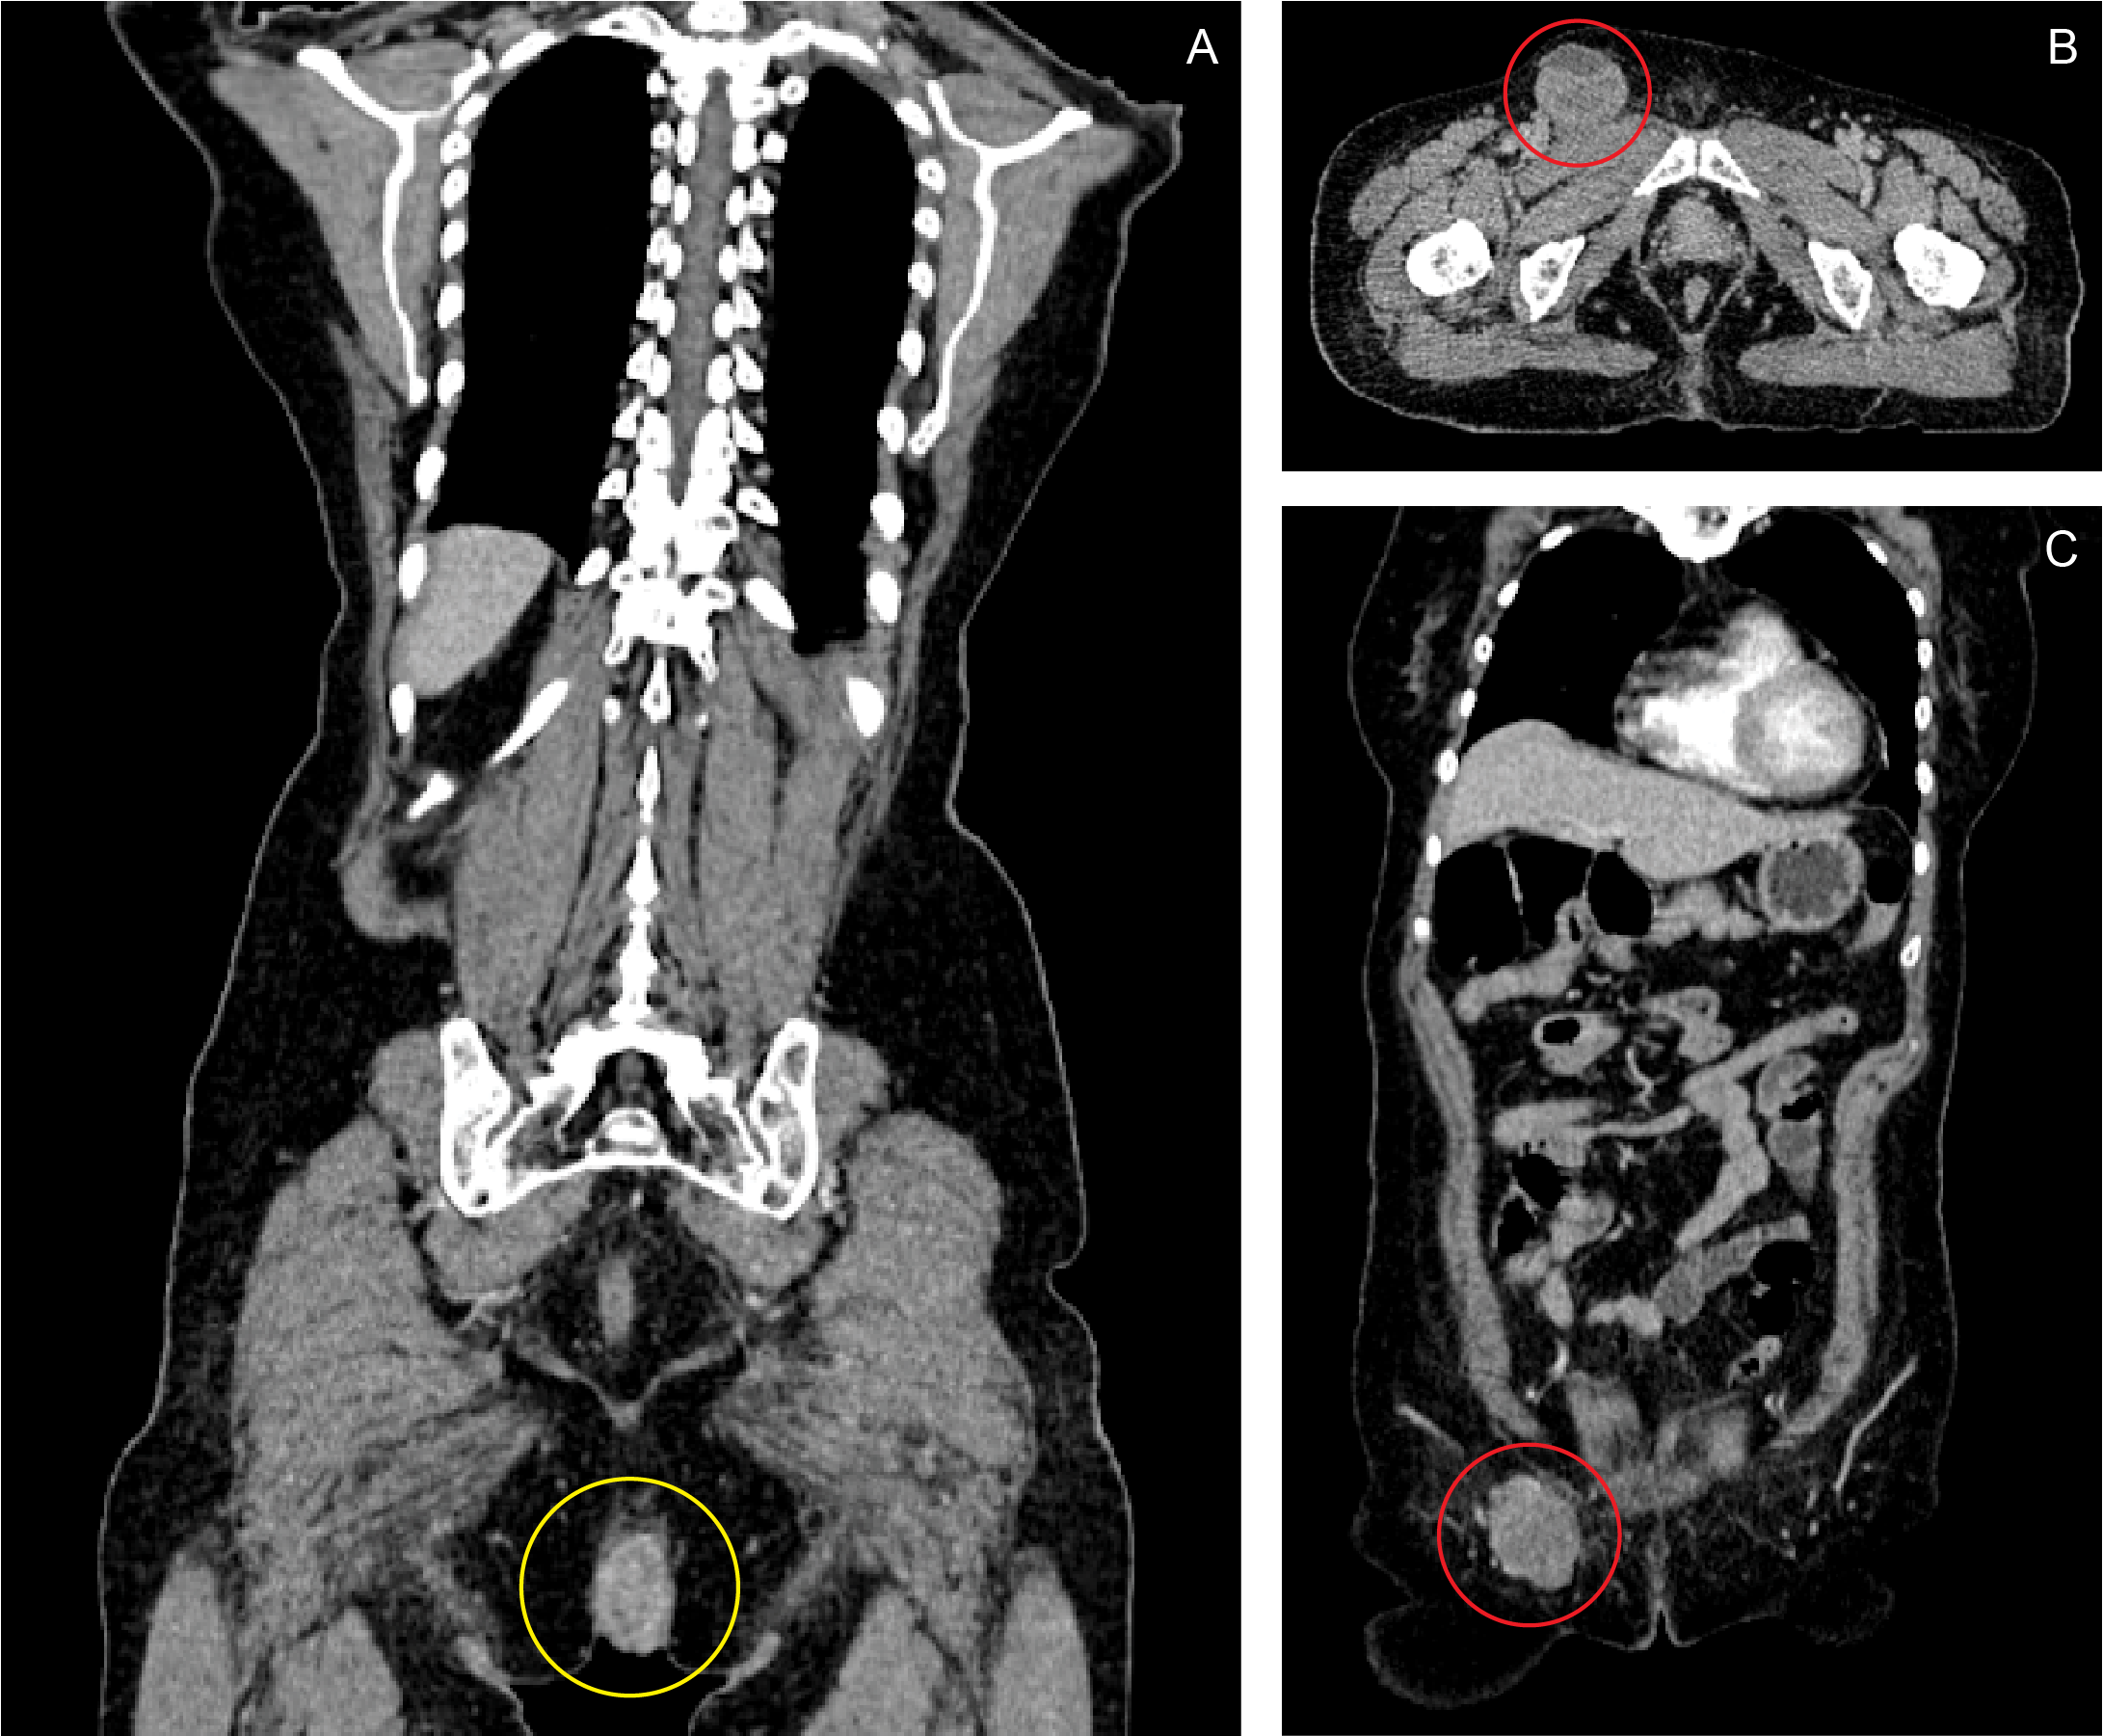

| Figure 1

Coronal (A, C) and axial (B) views of contrast CT scan of the whole abdomen. A fairly-defined, heterogeneously-enhancing, fungating mass, measuring 5.40 x 3.14 x 5.81 cm, is seen in the anal region, infiltrating the puborectalis muscle, anal sphincter and perineal muscles (A: yellow ring). A second, well-defined, lobulated, enhancing, hypodense mass measuring 5.29 x 4.58 x 4.33 cm is also noted at the right inguinal area (B, C: red ring).

A month prior to this admission, she went back to her first physician because the bleeding episodes had become more frequent, and the anal mass already measured around 6 x 7 x 6 cm by this time. The patient decided to pursue treatment in our hospital. A colonoscopy was done, which demonstrated that the base of the pedunculated anal mass was located at the right posterolateral aspect of the anal canal, extending from the anal verge and reaching up to the dentate line, with a base measuring 2 cm in diameter. No masses or other lesions were found from the cecum down to the rectum. A CT scan of the whole abdomen with contrast showed a fairly defined heterogeneously enhancing mass, measuring 5.40 x 3.14 x 5.81 cm in size and infiltrating the puborectalis muscle, anal sphincter and perineal muscles. A second, well-defined, lobulated, enhancing, hypodense mass measuring 5.29 x 4.58 x 4.33 cm in size was also noted at the right inguinal area. (Figure 1) The characteristics of both masses were consistent with an anal malignancy with perianal muscle infiltration and inguinal lymph node metastasis.